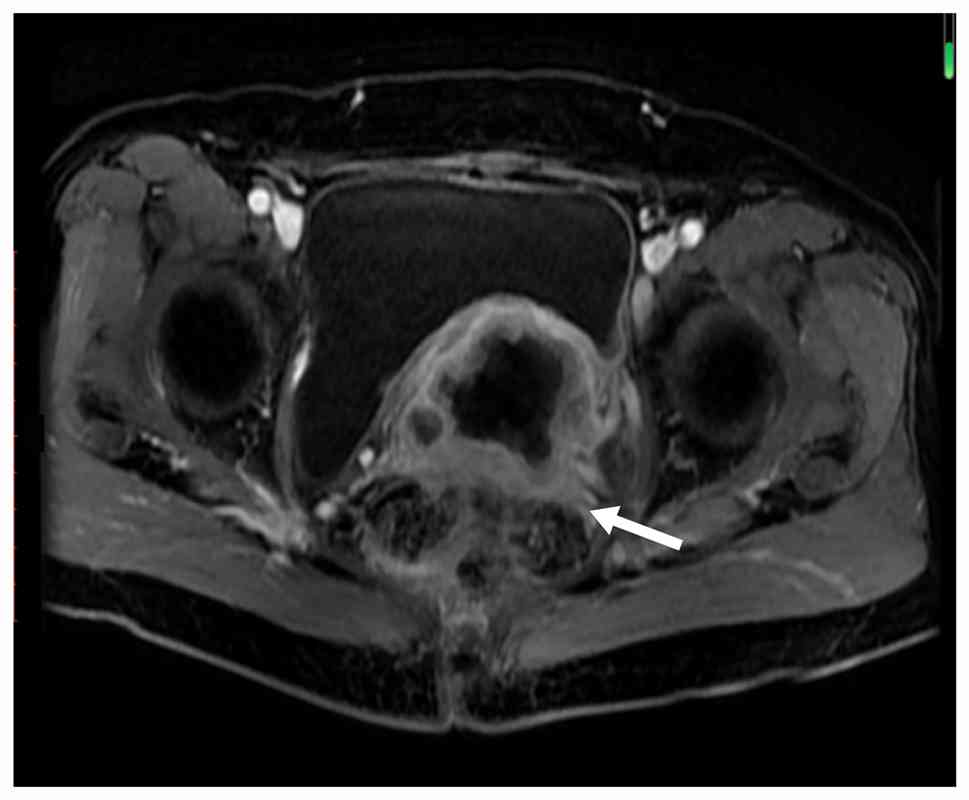

Examples of MRI diagnostic images from multiple patients are shown in Fig. 1, Fig. 2, Fig. 3, Fig. 4, Fig. 5. Fig. 1 shows an irregular soft-tissue mass in the cervical region, clearly visible on the axial sequence of T2-weighted fat-saturated imaging. The mass may suggest cervical lesions or tumors. Fig. 2 displays multiple lymph node metastases in the pelvic region on the axial sequence of DWI. The high-signal areas indicate that the lymph nodes might be affected by tumor metastasis. Fig. 3 reveals an irregular soft-tissue mass in the cervical region on the sagittal sequence of T2-weighted fat-saturated imaging. The mass is shown to have extended into the vaginal area, with the sagittal view aiding in the assessment of the lesion's longitudinal extent. Fig. 4 displays an irregular soft-tissue mass in the cervical region on T1-weighted enhanced imaging. The mass shows significant heterogeneous enhancement, suggesting that the lesion may be malignant. Fig. 5 illustrates a lesion in the cervical and vaginal regions on the sagittal sequence of T1-weighted enhanced imaging. The lesion area demonstrates heterogeneous enhancement, further indicating the possibility of a malignant tumor.

Diffusion-weighted imaging axial

sequence showing multiple lymph node metastases (white arrow) in

the pelvic region.

Figure 2.

Diffusion-weighted imaging axial sequence showing multiple lymph node metastases (white arrow) in the pelvic region.